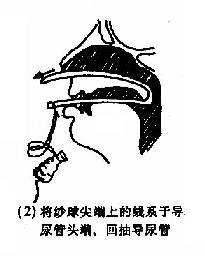

(2)后鼻孔填塞法(postnasal packing):先将凡士林纱条或消毒纱布卷迭成块形或圆锥形,长约3.5cm,直径约2.5cm,用粗线缝紧,两端各有约25cm长的双线,消毒备用。填塞时先收缩和表麻鼻腔粘膜,咽部亦喷有表面麻醉剂。用导尿管由前鼻孔沿鼻腔底部插入直达咽部,用镊子将导管从口腔拉出,导尿管尾端则留于前鼻孔外,再将填塞物上的双线系于导尿管,此时将填塞物由口腔送入鼻咽部,填塞于后鼻孔。为了减少患者痛苦,可用弯止血钳将填塞物在明视下送到悬壅垂的后上方,再将导尿管的鼻端向外拉紧。最后在前鼻孔处用一纱布球,将双线系于其上,以作固定,口腔端的线头可剪短留在口咽部,便于以后取出填塞物时作牵拉之用。后鼻孔填塞后,一般都需加行鼻腔填(图4-7)。鼻腔填塞物应于24~48小时内取出或更换,以防引起鼻窦及中耳感染等并发症。

图4-7 后鼻孔填塞法